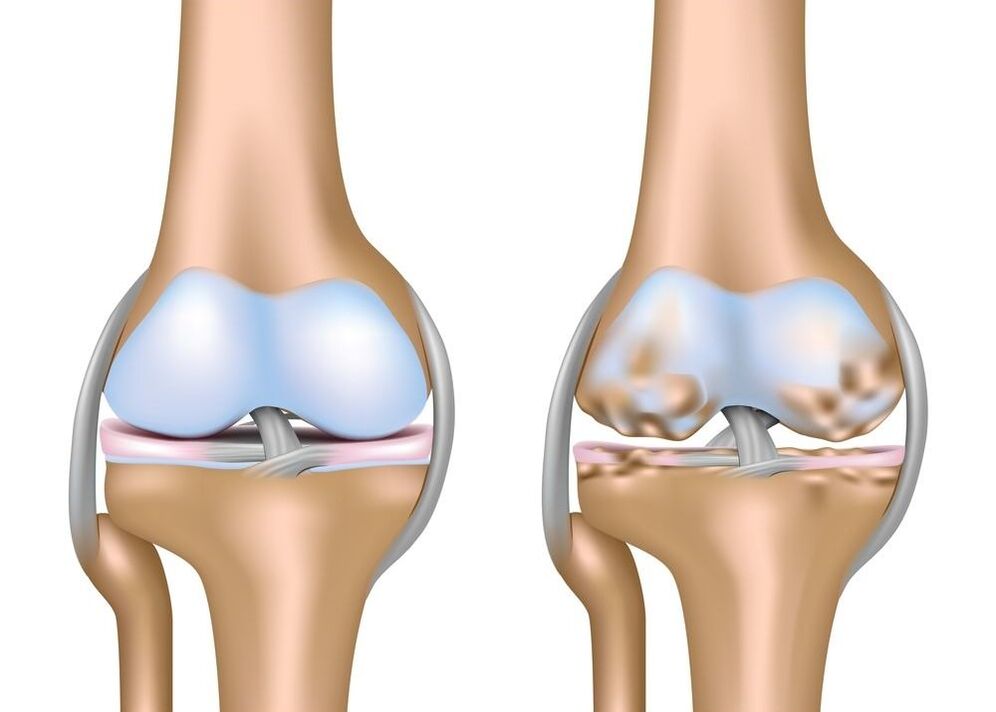

L'artrosi è una malattia articolare di natura degenerativa-distrofica con una lenta crescita della struttura cartilaginea e la proliferazione del tessuto osseo. Come risultato di questi cambiamenti patologici, si verifica la deformazione dell'articolazione interessata, la sua mobilità è compromessa e si verifica un forte dolore. Secondo le statistiche ufficiali, dal 10 al 20% delle persone nel mondo soffre di questa patologia. Si tratta di indicatori piuttosto significativi che aumentano ogni anno. Durante il processo di invecchiamento, nel sistema muscolo-scheletrico si verificano cambiamenti legati all’età, caratteristici della maggior parte delle persone di età superiore agli 80 anni. Tuttavia, solo una piccola parte di loro consulta un medico, preferendo l'automedicazione. È questo approccio che peggiora significativamente la prognosi per il recupero e aumenta anche la possibilità di disabilità.

A causa dell'influenza di uno o più dei fattori sopra elencati, inizia la graduale distruzione del tessuto cartilagineo che ricopre la superficie articolare dell'osso. Innanzitutto diventa più sottile, meno elastico e poi si rompe completamente. Il tessuto osseo subcondrale entra in contatto con la superficie dell'osso, provocandone la distruzione per attrito. La reazione protettiva del tessuto osseo è la sua proliferazione (soprattutto lungo i bordi articolari), che limita notevolmente la mobilità dell'articolazione e porta alla sua deformazione.

Le cellule delle articolazioni hanno una particolarità: danno una risposta rapida a qualsiasi lesione, anche lieve. Le cellule danneggiate sintetizzano attivamente citochine antinfiammatorie, motivo per cui la distruzione della cartilagine e delle ossa è caratterizzata da un'infiammazione asettica nella sinovia. Le frequenti ricadute della patologia portano ad un peggioramento dell'infiammazione, quindi le cellule dei tessuti duri iniziano a morire ancora più rapidamente, il che contribuisce alla progressione della malattia.

L'artrosi del ginocchio si manifesta con un caratteristico crunch, che si forma a seguito dell'attrito delle superfici articolari l'una contro l'altra. Il ginocchio inizia gradualmente a deformarsi a causa della crescita del tessuto osseo lungo i bordi. I pazienti cercano di limitare qualsiasi movimento, il che porta all'atrofia muscolare. Questo, a sua volta, rende l’andatura ancora più instabile e cauta. L’artrosi degli arti superiori è solitamente una conseguenza di lesioni o di artrite cronica. La deformazione più evidente si osserva nelle articolazioni interfalangee della mano. Sulle dita si formano i nodi di Bouchard e di Heberden e la mano stessa diventa quadrata.